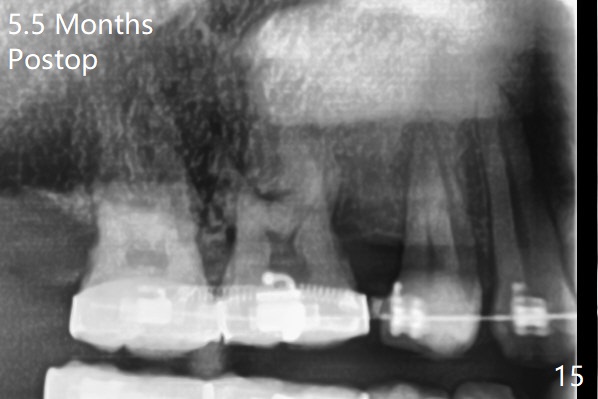

A 40-year-old man requests orthodontics after #17 and 32 extraction. UL5 is missing (Fig.1), while the upper midline deviates to the left (Fig.2 arrow) with crowding between UL2 and 3 (Fig.3). The main goal is to retract UL5 distal and move the upper midline to the right to alleviate UL anterior crowding. Implant will be not needed. To monitor potential root resorption associated with tooth movement, preop PAs are taken (Fig.4-7). The space for an implant at UR5 is narrow. UR4 needs to be distalized using UR7 or a miniimplant distal to UR7 as an anchor (Fig.8). UR4 and 3 will be repositioned to establish Class I occlusion (Fig.9). The space gained by UR4 distalization may be enough to correct the upper midline deviation and UL3 malposition (Fig.10). Brackets will be placed in the lower arch in spite of the normal alignment (Fig.11). UL2 and 3 brackets are unable to be engaged to 14 niti wire (Fig.12). Next visit try to engage UL2 bracket. If not, save the old wire for possible future reuse. Closed spring is placed with 18 ss wire <3 months post banding (coronavirus). Three weeks post closed spring between UR4-7, UR3,4 are being distalized (Fig.13). Distalization of UR4 is not much in 5.5 months (Fig.14,15). It seems necessary to use a miniimplant distal to UR7 as an anchor (Fig.16 white circle), place a long hook mesial to UL4 (more or less root movement instead of tilt) and place the same closed spring between the anchor and hook. In spite of the fact that UR4 seems to have been completely distalized and that UR2 is being distalized 8 months post banding (Fig.18), a 8 mm long mini-implant is placed in the maxillary tuberosity with minimal local anesthetic (Fig.17,19). A longer closed spring (18 mm) is placed between the implant and UR3 hook (Fig.20). Next appointment a lingual button will be placed at UR4 for rotation, while a post hook mesial to UR3 for torque. UR3 distalizes with the help of UR mini-implant, which is unfortunately loose. Next visit place lingual button at UR4 (Fig.21 arrow) to distalize the lingual cusp. Crimpable power hook is placed mesial to UR2 for distalization (for root torque, Fig.22). If it works, remove the wire and reposition the hook for UR1 next visit. UR2 is distalized in one appointment (~ 1 month, Fig.23, as compared to Fig.22). With lingual button at UR4, rotation seems to have been corrected shortly (Fig.24 arrow).